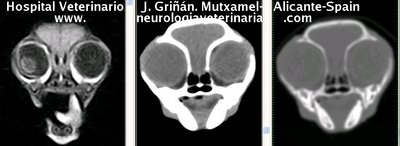

Se muestran cortes transversales de Resonancia Magnética (imagen a la izqda del lector), TC contrastado para tejidos blandos (imagen del centro) y TC contrastado para tejidos duros (imagen de la derecha del lector).

Nótese como la Resonancia supera al TC en el contraste de tejidos blandos (encéfalo y médula espinal) y en el de líquidos (ojo y líquido cefalorraquídeo), mientras que el TC supera a la resonancia en el contraste de tejidos duros (hueso) y aire (senos, cavidad nasal y bullas)

Cortes a nivel de los lóbulos cerebrales parietales